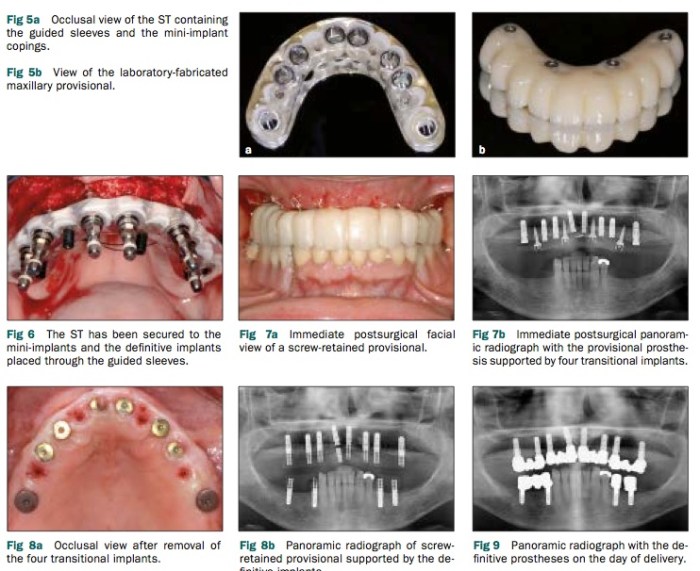

關於這篇文章提到的方式, 在我剛畢業的時候我就有看過了, 但在paper上比較少看到有系統地去設計使用這樣的方式做單顎或是全口的植牙重建治療. 因為重點都在圖表所以也是請看圖說故事, 其重點就是若有transitional implant (犧牲打的implant), 不但可以讓患者在植牙的時候手術模板夠穩定, 還可以讓臨時假牙穩定有作用.